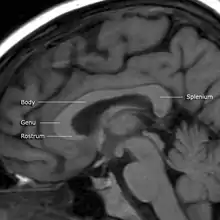

MRI of corpus callosum and its named parts

The corpus callosum has four main parts; individual nerve tracts that connect different parts of the hemispheres. These are the rostrum, the genu, the trunk or body, and the splenium.[4] A narrowed part between the trunk and the splenium is known as the isthmus. Fibres from the trunk and the splenium known together as the tapetum form the roof of each lateral ventricle.[6]

The front part of the corpus callosum, towards the frontal lobes is called the genu ("knee"). The genu curves downward and backward in front of the septum pellucidum, diminishing greatly in thickness. The lower much thinner part is the rostrum and is connected below with the lamina terminalis, which stretches from the interventricular foramina to the recess at the base of the optic stalk. The rostrum is named for its resemblance to a bird's beak.

The end part of the corpus callosum, towards the cerebellum, is called the splenium. This is the thickest part, and overlaps the tela choroidea of the third ventricle and the midbrain, and ends in a thick, convex, free border. Splenium translates as bandage in Greek.

The trunk of the corpus callosum lies between the splenium and the genu.